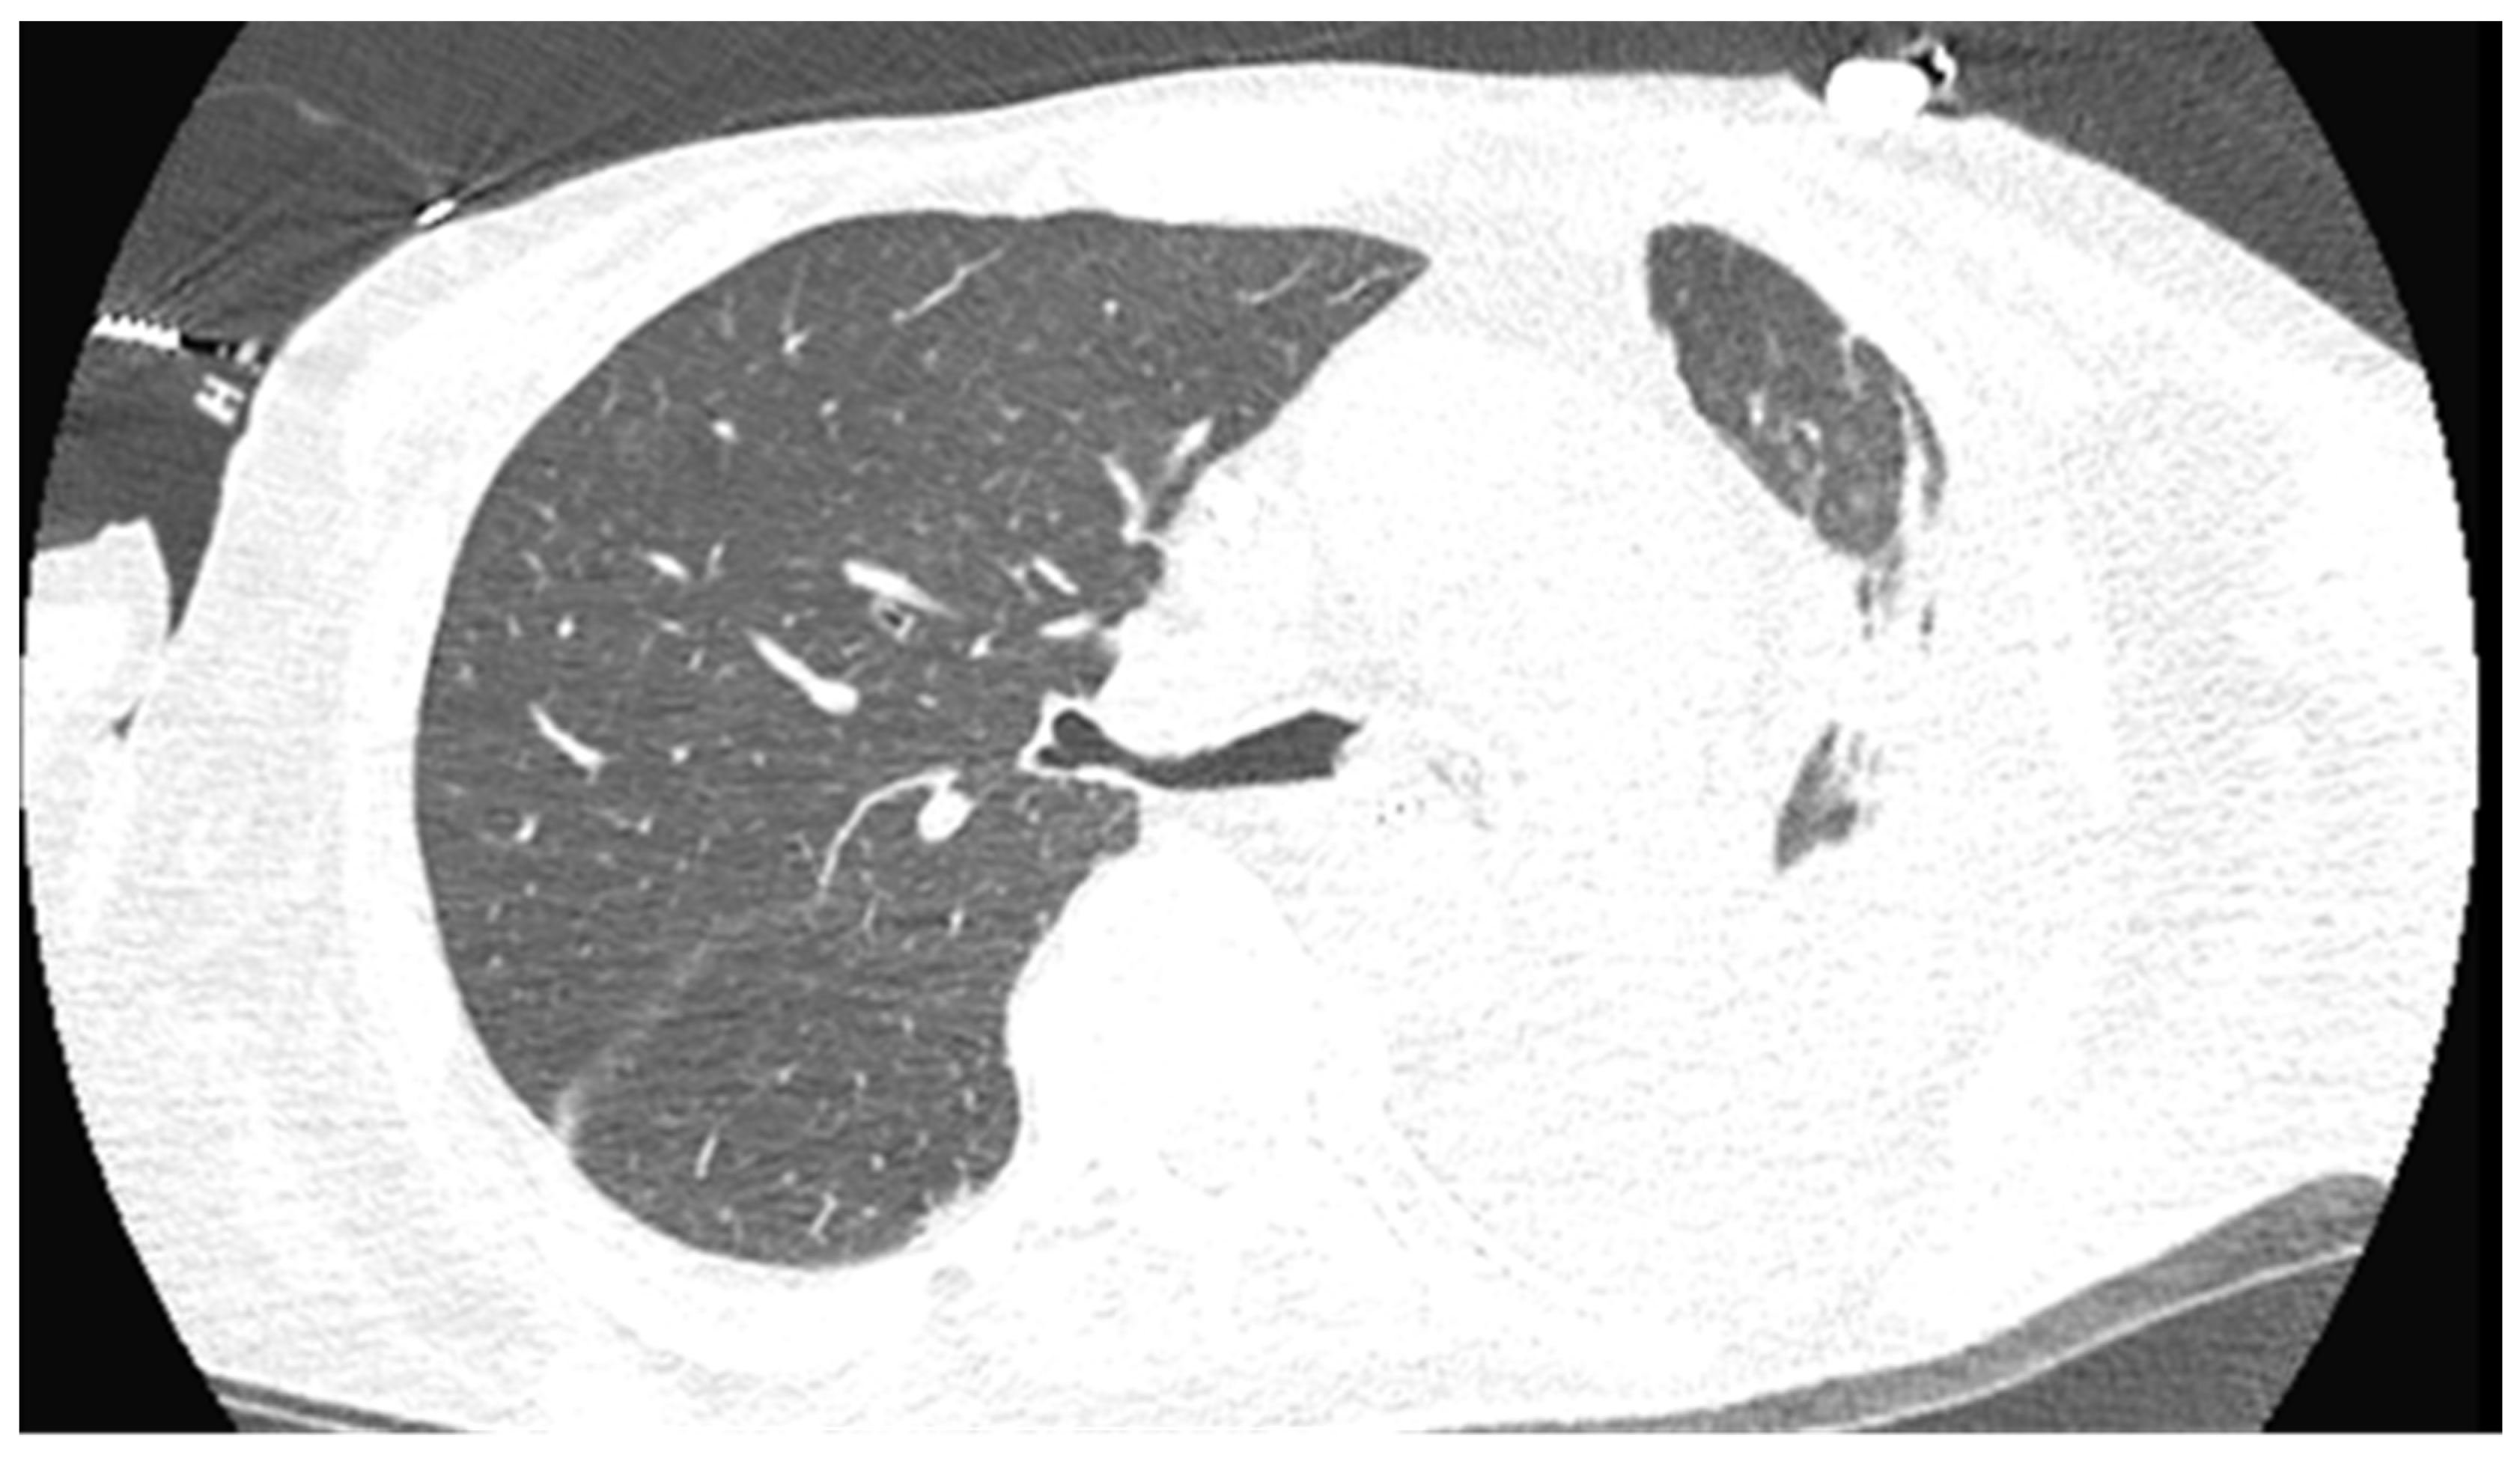

2. Case Presentation